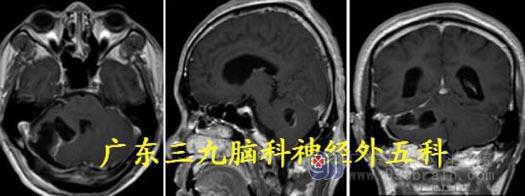

头颅MR:小脑蚓部、四脑室区示类囊状长T1 长T2 病灶,同时可见多发流空信号影,

并可见一粗大引流血管,病灶范围约40.8mm×40.8mm×52.7mm,增强后环壁不均匀强

化,边缘不光整。考虑血管母细胞瘤及幕上梗阻性脑积水。

MR 灌注测值395.61±232.75ml/100g/min;提示病灶高灌注,血供极其丰富。